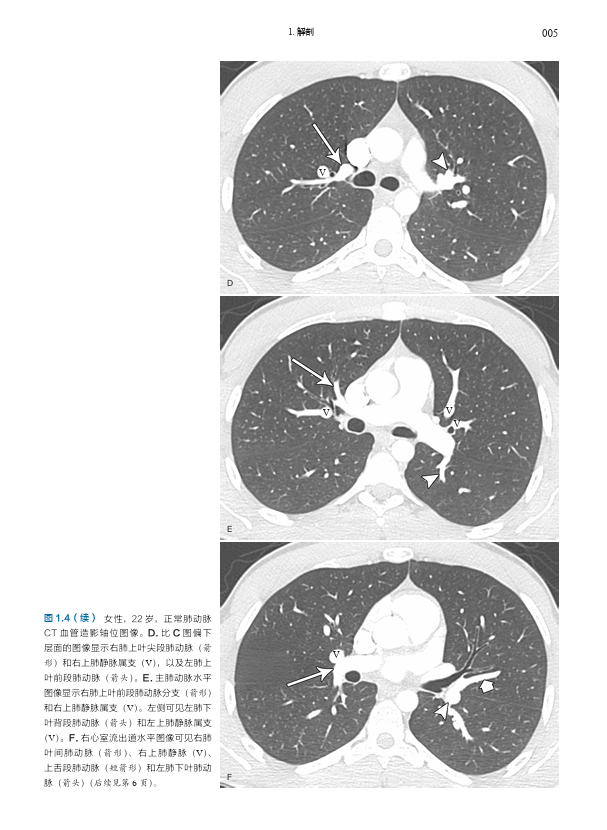

本书是由哈佛大学医学院附属麻省总医院 Conrad Wittram 编写的有关肺血管疾病的综合影像图谱,内容包括肺血管正常解剖、先天性肺部疾病和心脏疾病的肺血管变化、特定类别的肺血管疾病(如栓塞、血栓形成、血管炎、动脉瘤和静脉瘤、感染、肿瘤、肺高血压等)、创伤与介入治疗相关肺血管问题,以及全身和肺部疾病的肺血管变化的影像学表现及特点。本书内容翔实,编排简明清晰,图文配合,每一页上都有详细的、清晰标记的高质量影像图,展示了 X 线片、血管造影、多层螺旋 CT、MRI、超声和核素显像等多种成像方式下的影像表现,配以绘图及指示性箭头等,使得影像特征更加清晰;文字精要,突出了最相关的重要信息。

肺动脉 001